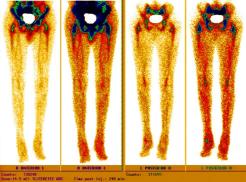

Nuclear Scan Images of Lower Torso & Lower Legs

These images were captured in order to determine why Liam’s bones broke so easily playing a video game and to also determine if there

was any Osteomyelitis. This is the diagnosis report from the scan. "There is mild increased activity noted in the lateral side of the left

ankle. However the patient does have a cast on the left leg. This uptake can be secondary to either inflammatory or infectious change within

either the skin or adjacent bone." Various contrast were used to enhance image details. The last images reminds one of the Shroud of Turin.

Hummm, makes one wonder... ;-)